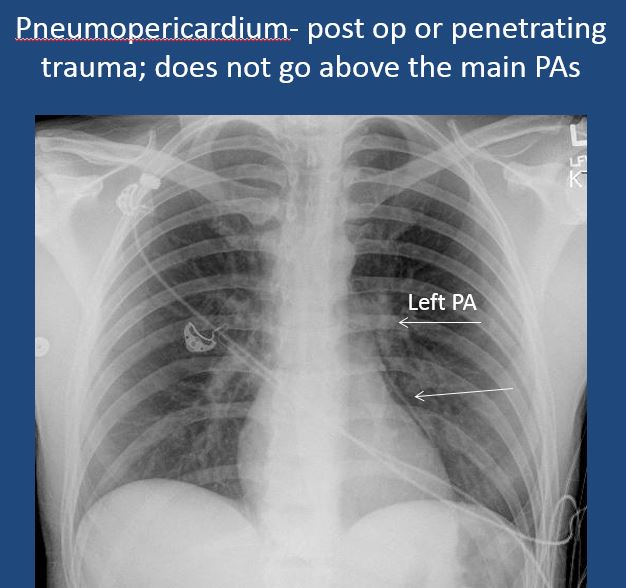

There is pneumopericardium. [Yes/No]